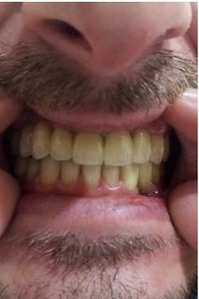

Установка коронки из диоксида циркония

Доктор: Базаян Арсен Андреевич